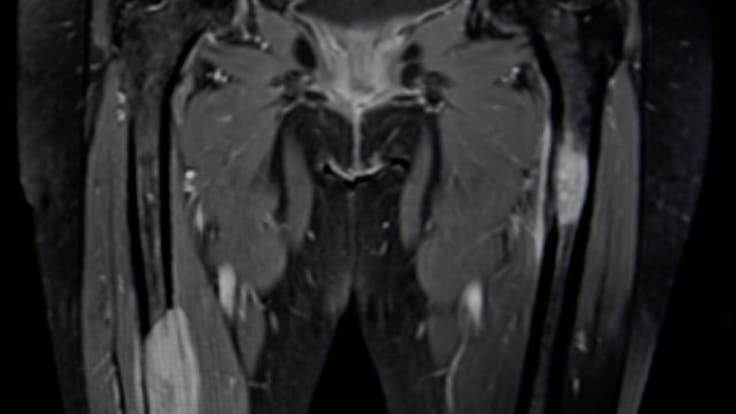

une IRM pelvienne ou une uro-IRM si l'uroscanner est contrindiqué;